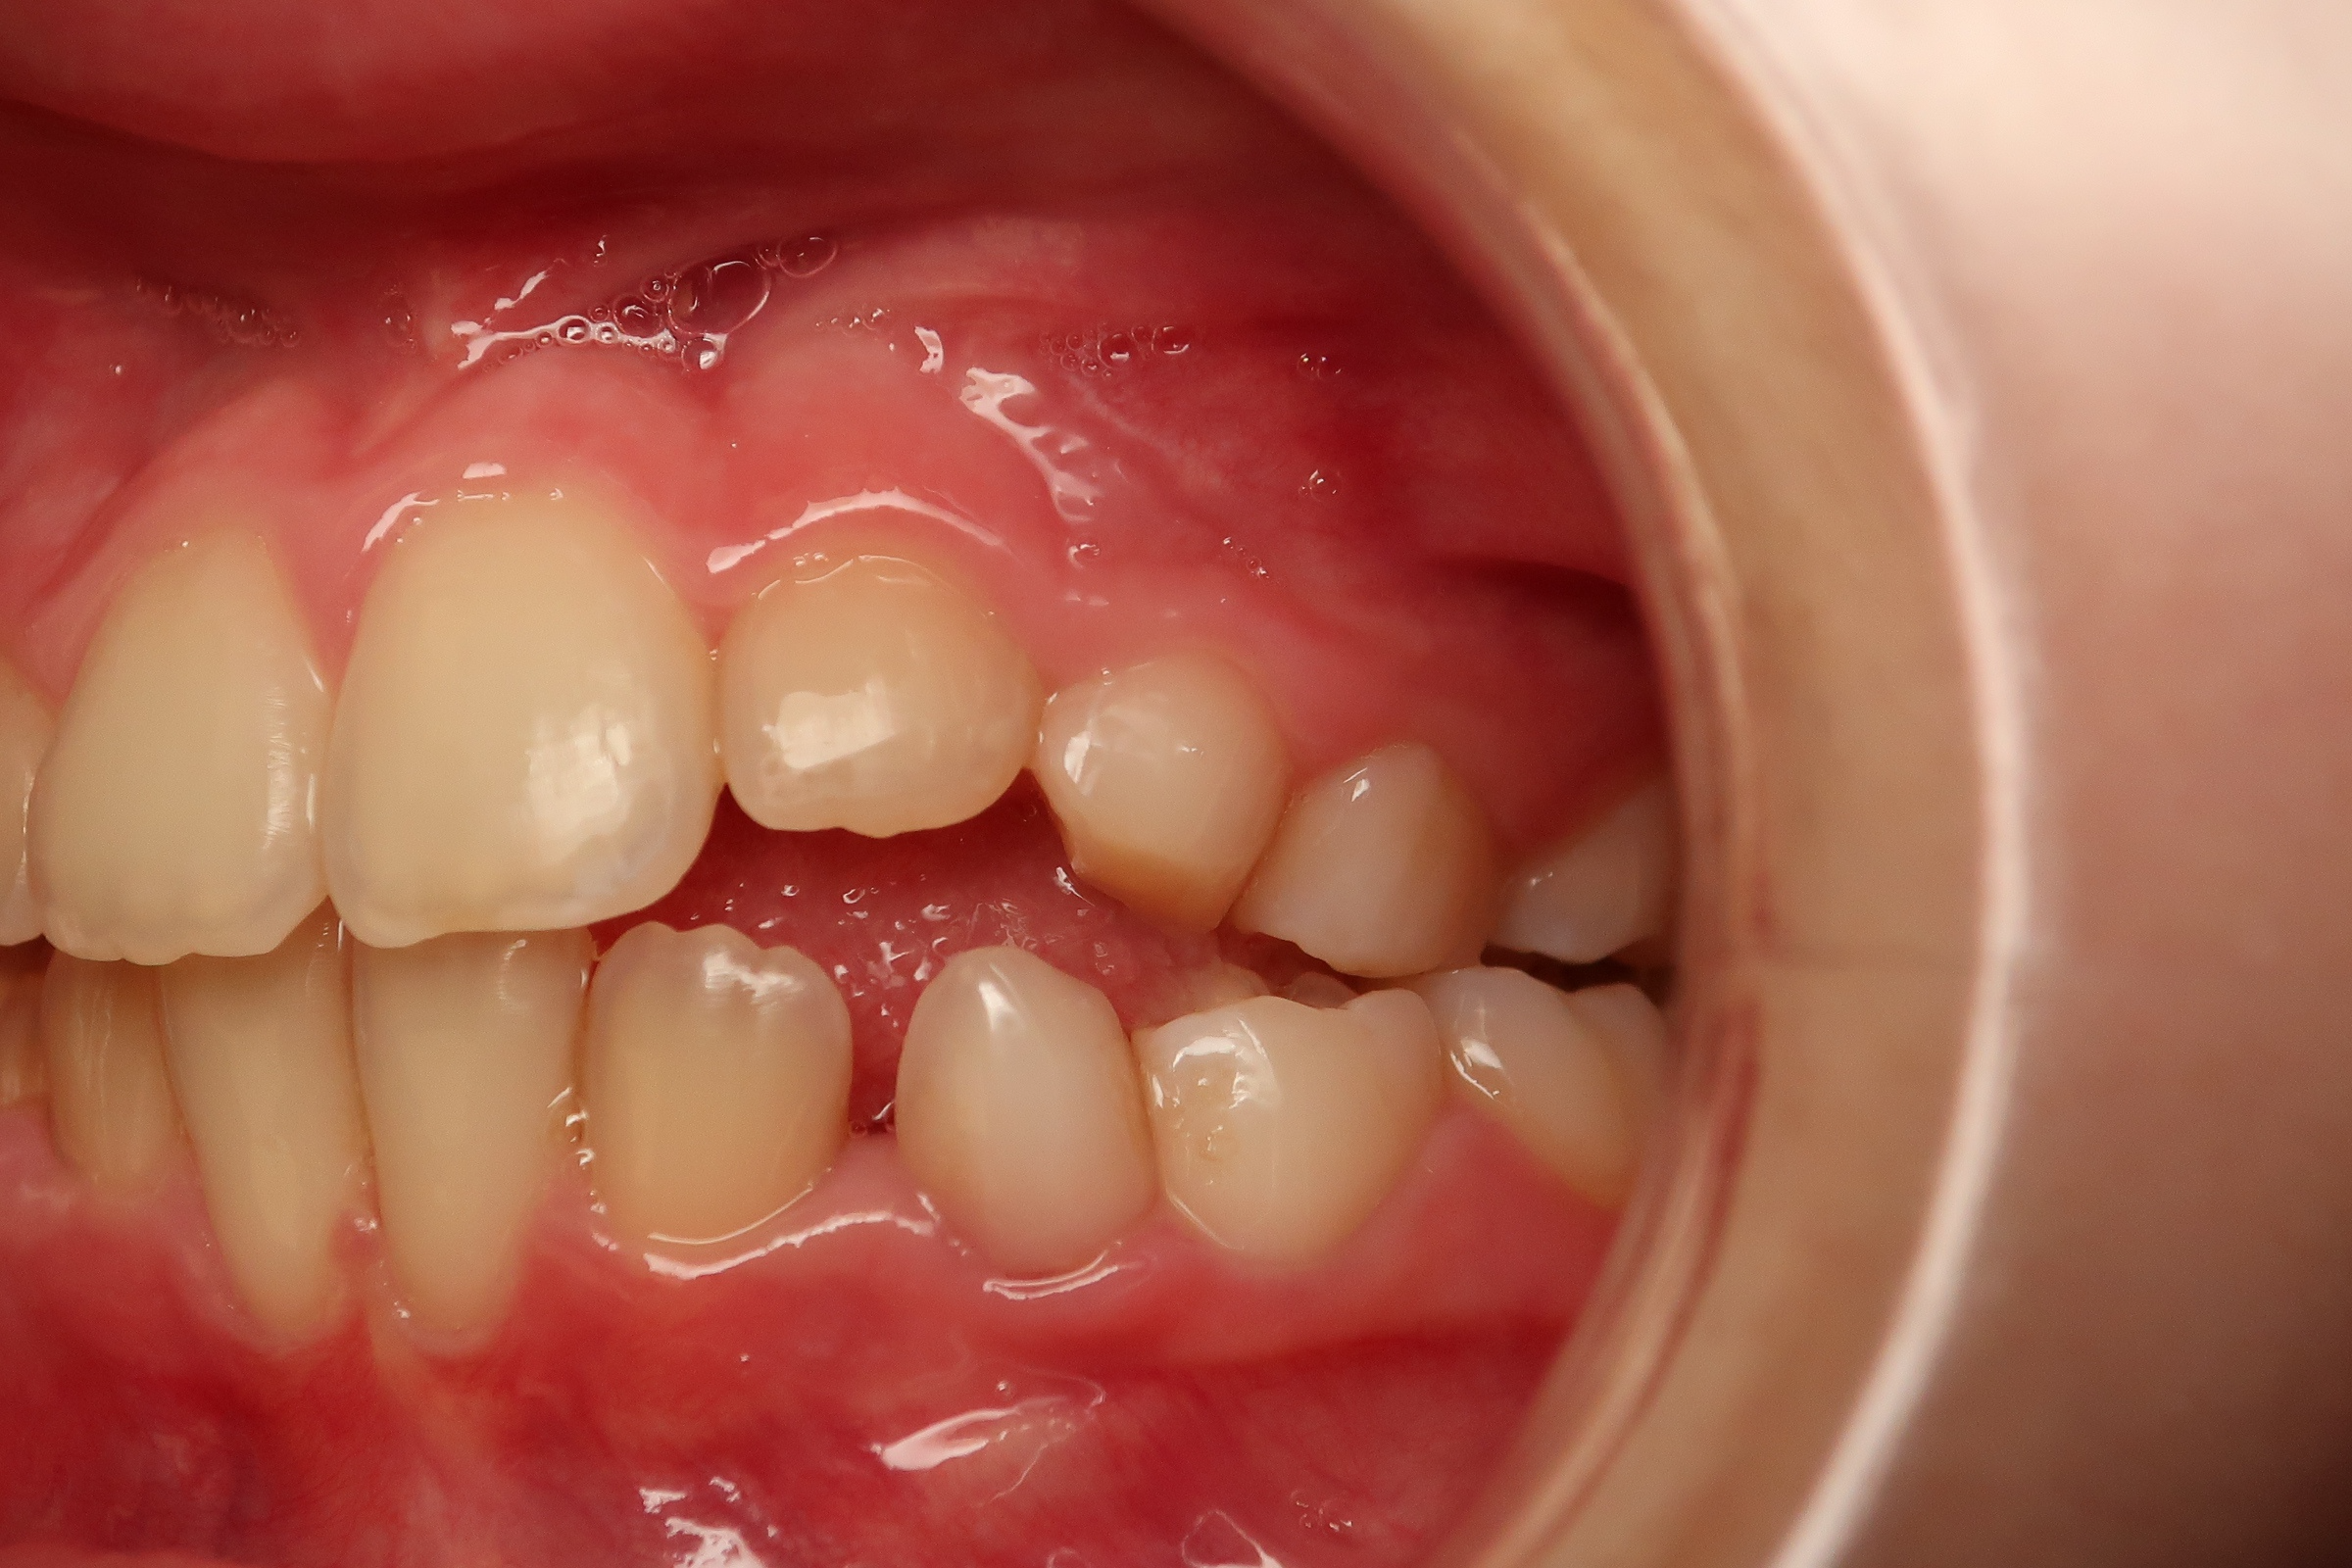

appareillage mobile pendant 5 mois

surveillance évolution de la dentition pendant 27 mois